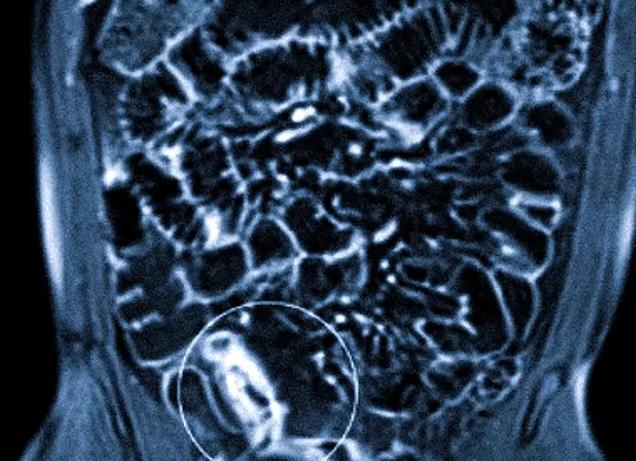

ЖКТ (желудочно-кишечный тракт) отличается особым строением. Диагностика данной системы недоступна для общего визуального осмотра, поэтому следует задействовать специальные компьютерные технологии. Следует отметить, что диагностика тонкой кишки (либо других отделов кишечника) используется редко, но является наиболее эффективным. Магнитные поля сканируют тонкие кишки, ткани внутренних органов делают их фотографию в формате 3D.

Данные, которые смог считать аппарат, поступают на общий компьютер. Снимки, сопроводительная информация к ним отображаются на мониторе. После выведения информации, ее обработки, она снова дублируется на мониторе.

Давайте разберём и то, что показывает любой снимок тонкого кишечника, сделанный с использованием метода магнитно-резонансной томографии. Но сначала стоит упомянуть, что все данные, считываемые аппаратом, отправляются на компьютер. Все снимки отображаются на мониторе специалиста, где и происходит их изучение, а также обработка. Аппараты для МРТ проработаны для мелочей, существует система, которая автоматически записывает информацию, что позволяет восстановить снимки даже при возникновении сбоев. Врачи, изучив снимки, могут:

МРТ тонкого кишечника – высокоточный метод диагностики, благодаря которому можно выявить нарушения желудочно-кишечного тракта любой этиологии. Магнитно-резонансная томография является самым информативным и безопасным способом обследования. Неоценимая эффективность МРТ отмечается в выявлении болезни Крона, неспецифического язвенного колита, новообразований в тонком кишечнике, и других патологических процессов. Примечательно, что при обнаружении болезни Крона, на экране монитора МРТ возникает не только изображение пораженных кишечных сегментов, но и разграничение фиброзных изменений. Данная методика позволяет вычислить фазу воспаления, что в дальнейшем способствует правильному лечению.

Технология магнитно-резонансной томографии основывается на воздействии сильных магнитных полей, что, в отличие от рентгенологических методик, не приносит вреда организму пациента. Принцип оборудования МРТ предусматривает визуализацию органов и тканей на экране в трехмерном изображении. Таким образом, 3d-реконструкция клинической картины позволяет детально рассмотреть исследуемый орган во всех ракурсах, осуществить проверку брыжеечных лимфоузлов, и выявить аномалии жировой клетчатки. Для повышения точности исследования применяется МРТ с контрастом или гидро МРТ с двойным контрастированием. Парамагнитное контрастное вещество вводится внутривенным или пероральным путем непосредственно перед процедурой обследования.

Магнитно-резонансная томография – бесценное достояние медицины, с помощью которого можно своевременно распознать даже малейшие отклонения от нормы. Сканерная система МРТ отображает достоверные данные исследуемого органа, дает возможность определения стадии болезни и помогает вычислить степень вовлеченности соседних органов в зону первичного патологического очага.

МРТ-диагностика выявляет:

врожденные аномалии строения тонкого кишечника; патологические заболевания (неспецифический язвенный колит, болезнь Крона); новообразования любого характера; места локализации раковых метастаз;

наличие инородных тел в тонком кишечнике